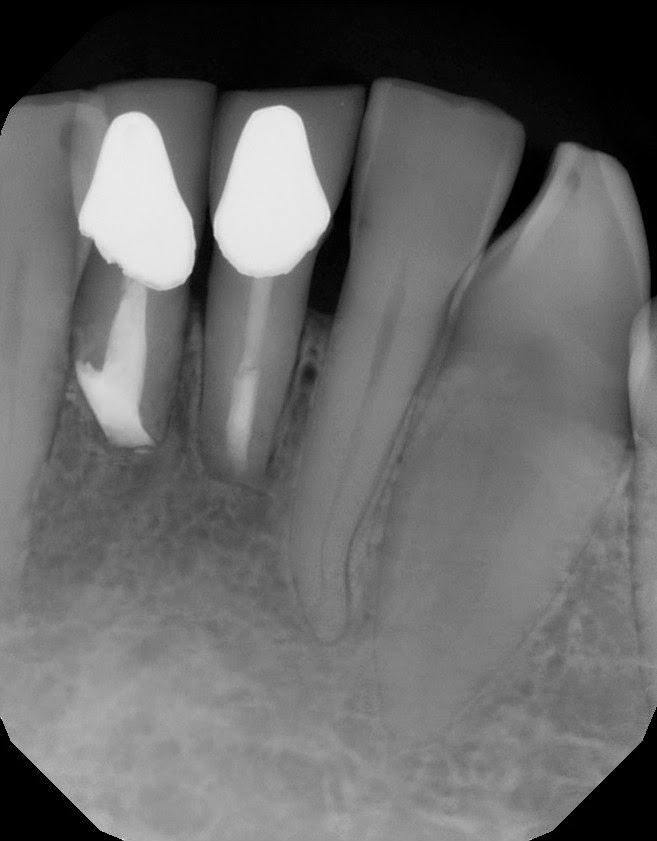

PostOp Apicoectomy

Because of the resorption at the apex of #25, a traditional root end preparation and filling was not possible with removing too much tooth structure. In this case, we bonded Geristore on the root apex and tried to "cap" the apex. Retrofill #24 is MTA.